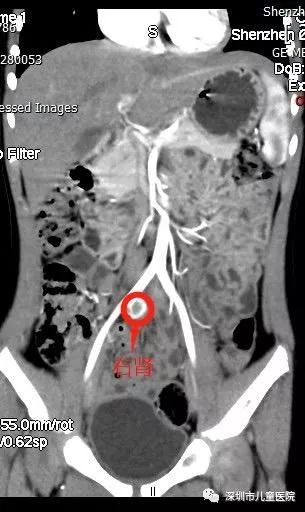

果不其然,这次,在她的右侧盆腔发现了一个蚕豆大小的、功能很微弱的肾脏。原来,小美的右肾并没有凭空消失,而是“跑”到了盆腔,在这里安了家。

至此,谜团终于被揭开了:

她的右肾发育不良,右肾异位(盆腔),右侧输尿管异位开口。 来,小美的右肾并没有凭空消失,而是“跑”到了盆腔,在这里安了家。

手术团队给小美做了个微创手术:在她的腹部开了三个5mm的小孔,在腹腔镜下将右侧这个发育不良的肾脏和一部分与之相连的输尿管切除掉。